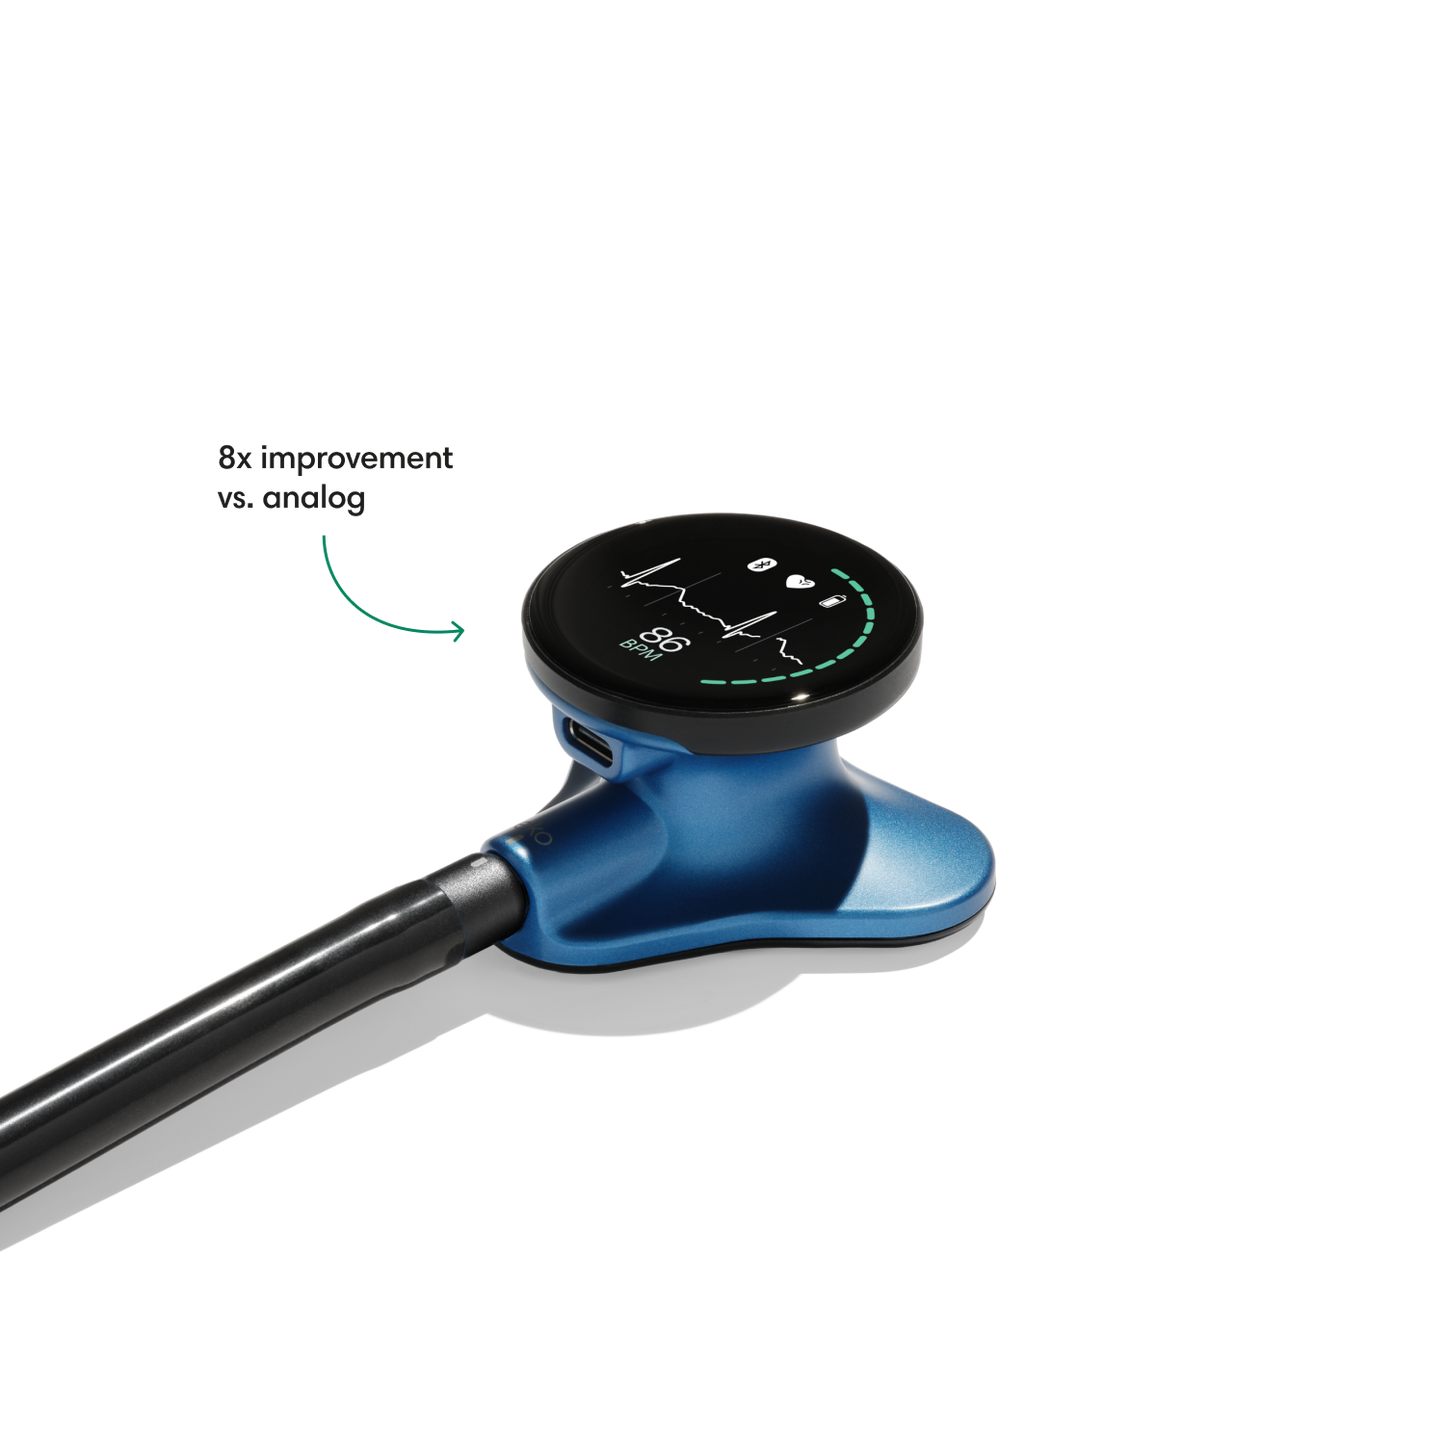

Instead of using a hollow tube like with an analog stethoscope, heart and lung sounds are delivered digitally through ear tip speakers. This results in unparalleled audio quality and sound cancellation.

- Reduces background noise 8x better vs. a typical analog stethoscope.